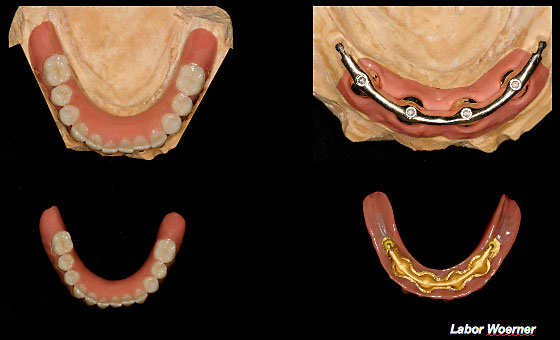

Fall: Implantatgetragene Stegarbeit bei zahnlosem Unterkiefer

Ausgearbeiteter Steg und Anpassung der Unterkieferprothese

Eingegliederter Steg

Schlussbild - Implantatgetragene Unterkieferprothese

Zahnloser Unterkiefer mit Brückenversorgung